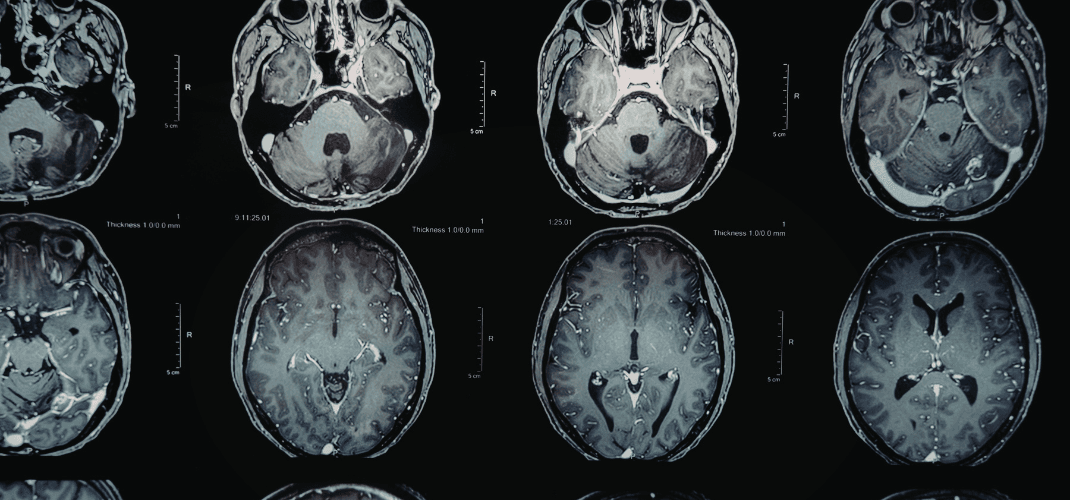

In mild traumatic brain injury litigation, one of the most persistent challenges is the gap between what a patient experiences and what standard imaging shows. When a routine MRI or CT scan returns "within normal limits," it is not the end of the neurological inquiry. For a qualified neuroimaging expert, it is frequently the beginning of a more nuanced evaluation.

Conventional MRI and CT were not designed to evaluate the integrity of white matter microstructure—the vast network of axonal pathways that connects regions of the brain and underlies cognitive function.

Diffusion Tensor Imaging (DTI) operates differently. Rather than producing a conventional anatomical image, DTI measures the movement of water molecules through the white matter tracts.